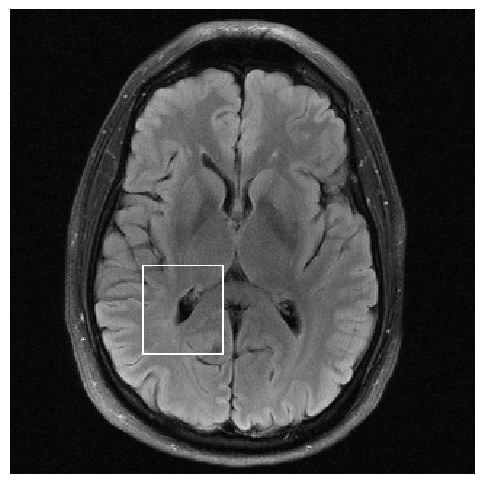

Figure 6: Examples of reconstruction results. Rows 1, 3, and 5: The reference (GT) fully sampled image, the reconstructed images obtained by the three models (1-3), NPB-REC, baseline, E2E-VarNet trained with Dropout, and the Std. map derived from our method for example from the knee dataset, the brain dataset, and the brain dataset sampled with radial mask L=50𝐿50L=50, respectively. Rows 2, 4, and 6: The corresponding annotated ROIs of the cartilage, edema, and nonspecific white matter lesion respectively.

Fig. 6 depicts the reconstruction results obtained by (1) our NPB-REC approach, (2) the baseline, and (3) Monte Carlo Dropout, for examples of both the knee (row 1) and the brain (rows 3 and 5) datasets. The first two examples were obtained by the models that trained on brain data and were tested on knee data (row 1) and vice versa (row 3). In knee images, all three models exhibit minimal differences in handling pronounced folding artifacts. However, our approach demonstrates superior reconstruction performance for anatomical annotations or pathological regions, labeled by radiologists, in terms of both PSNR and SSIM. The last example is a reconstructed brain image that was obtained by the three models, where the k-space input is undersampled by a radial mask with L=50𝐿50L=50. Table 2 presents the mean PSNR and SSIM metrics, calculated over the whole inference knee dataset, for the three models that were trained on brain data. The NPB-REC method shows a considerable improvement in the generalization ability on knee data for higher acceleration rates R=8𝑅8R=8 and R=12𝑅12R=12 in both annotation regions and the whole images. However, both the baseline and Dropout methods show a slight improvement in the metrics in the case of a small acceleration rate R=4𝑅4R=4. Table 3 shows the results of the inverse experiment, i.e. calculating the mean PSNR and SSIM metrics over the whole brain inference set for the three models that were trained on knee data only. The generalization capability of the three models in the case of an anatomical distribution shift from the knee to the brain is better than the opposite scenario. This is not only measured quantitatively by the SSIM and PSNR metrics, but also visible in the predicted reconstructions. For instance, the brain MRI reconstructed images exhibit fewer artifacts than the produced knee images, as shown in row 1 vs. row 3 in Fig. 6.

Table 3 presents the mean PSNR and SSIM metrics calculated over the whole inference knee dataset that were obtained by the three models, where the k-space input is undersampled by a radial mask with L=50𝐿50L=50 and L=40𝐿40L=40. Although the NPB-REC approach improves the accuracy of reconstruction when the metrics are measured on the whole image, it doesn’t yield the best performance on the annotation ROIs. However, it is still able to reconstruct high-quality images while preserving the important anatomical content in these annotations. This can be clearly observed in the last row in Fig. 6, where the topmost part of the ROI image predicted by NPB-REC is preserved, in contrast to the other benchmarks.